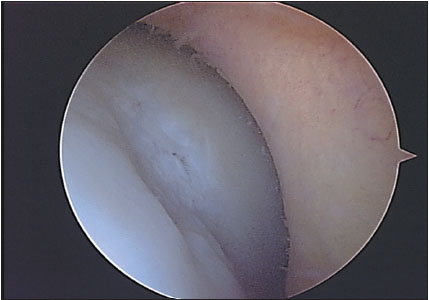

Todos los pacientes que realizaron su RM de rodilla en el Servicio de Diagnóstico por Imágenes del Hospital Británico, y luego fueron operados de su rodilla en el mismo Centro durante el mes de Abril de 2009, fueron incluidos en el presente trabajo. Es un estudio con un diseño transversal, con recolección de datos retrospectiva, nivel de evidencia III. Un total de 43 pacientes fueron incluidos. Dos pacientes fueron excluidos del análisis por alteración de la imagen de resonancia, uno por artefacto del movimiento durante el estudio y el otro por artefacto producido por material de osteosíntesis colocado en la rodilla en una intervención previa. De los 41 pacientes evaluados en el estudio, el promedio de edad fue de 50 años (21-71). Fueron 27 hombres y 14 mujeres evaluados. El intervalo de tiempo promedio entre la realización de la RM y la cirugía fue de 63 días (6-275 d). Veintinueve pacientes (70,73 %) fueron intervenidos dentro de los 2 meses de realizada la RM. Se realizó una revisión de las historias clínicas para corroborar que ningún paciente refirió alguna lesión durante ese intervalo de tiempo. En todos los casos se realizó una RM con un equipo Philips de 1,5 Tesla, realizando en todas ellas cortes de reconstrucción axial, coronal y sagital, para evaluar adecuadamente la articulación en toda su extensión. Cada estudio de RM fue analizado en forma retrospectiva por dos observadores ciegos de los resultados obtenidos luego en la cirugía, ambos trabajaron en forma conjunta. Uno de los evaluadores (M.C) es médico de planta del Servicio de Diagnóstico por Imágenes del Hospital (especialista en RM músculo esquelética); el otro evaluador (L.C) es Jefe de Residentes de Diagnóstico por Imágenes del Hospital. Ambos estudiaron cada caso en particular, y debían valorar el cartílago en cada zona articular y establecer un único resultado. Seis superficies articulares fueron evaluadas: rótula, tróclea, cóndilo femoral medial y lateral, platillo tibial medial y lateral. El cartílago articular fue clasificado en la RM y en la artroscopia de acuerdo a la clasificación de Johansson. (7) El Grado 0 indica cartílago intacto; grado 1 ablandamiento o edema de cartílago; grado 2 fibrilación de cartílago; grado 3 ulceración superficial o fisura que comprometen menos del 50% del espesor del cartílago; grado 4 ulceración profunda o fisuras que comprometen ás del 50% del espesor de cartílago; grado 5 lesión de espesor completo con hueso expuesto; grado 6 lesión en espejo, con hueso expuesto en ambas superficie enfrentadas. Todas las lesiones condrales debieron ser confirmadas en al menos 2 cortes de RM. Se confeccionó en cada caso un registro escrito de cada paciente con los grados de lesión condral en cada superficie. (Ver Figs. 1 a 4)

Figura 2: Lesión condral de espesor mayor al 50 %. Corresponde a un grado 4.